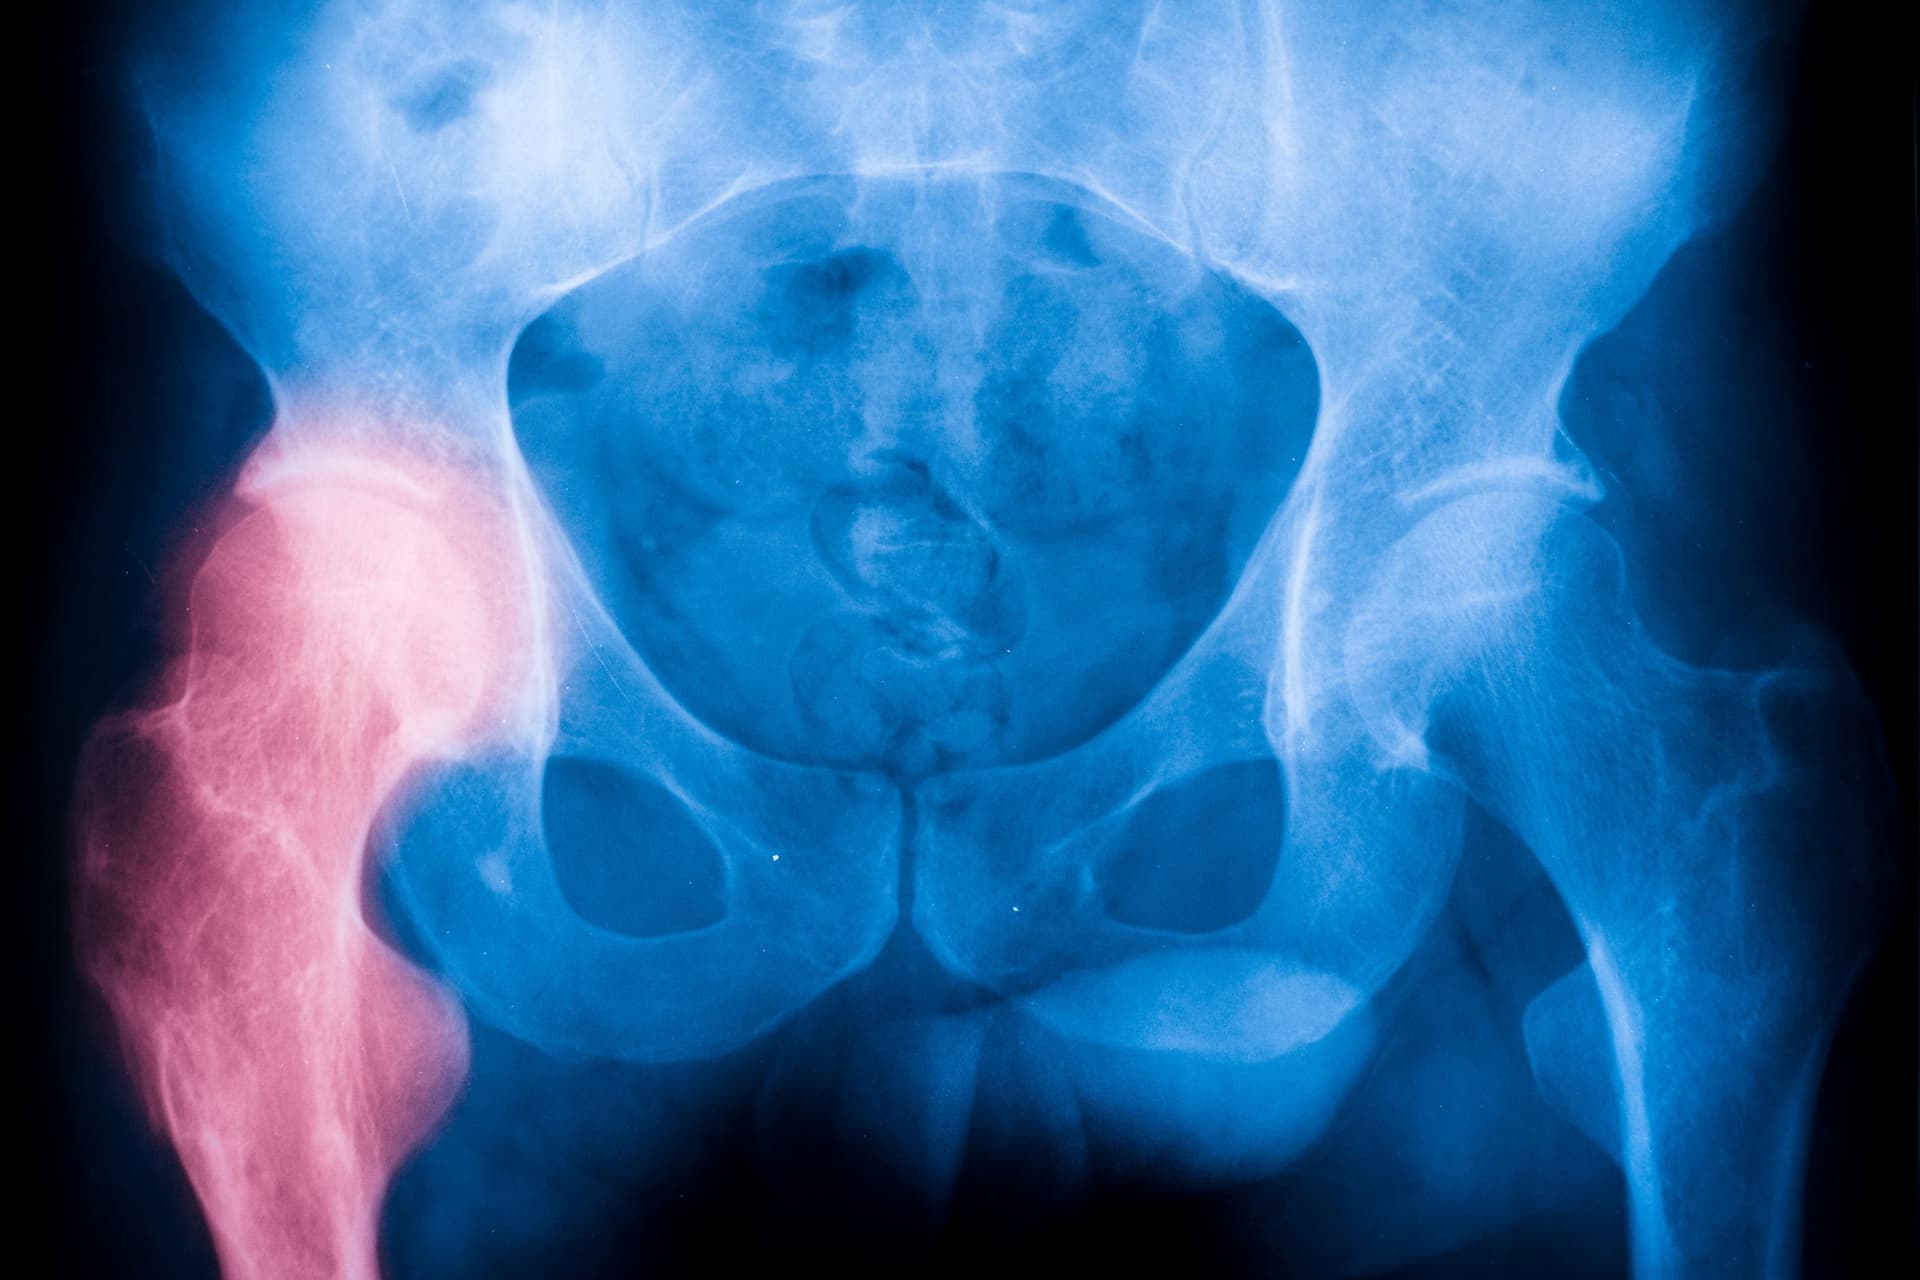

Η αρθρίτιδα του Ισχίου είναι η φθορά- καταστροφή του χόνδρου της άρθρωσης του ισχίου. Οι δύο βασικές μορφές της αρθρίτιδας ισχίου είναι η Οστεοαρθρίτιδα (ΟΑ) και η Ρευματοειδής Αρθρίτιδα (ΡΑ).

Οι ακτινογραφίες είναι χρήσιμες για την παρακολούθηση της εξέλιξης της ρευματοειδούς αρθρίτιδας και των βλαβών της στις αρθρώσεις με την πάροδο του χρόνου.  Οι υπέρηχοι και η μαγνητική τομογραφία MRI βοηθούν στην εκτίμηση της σοβαρότητας της νόσου.